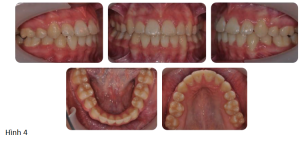

Kết quả điều trị được thể hiện ở Hình 4.

Tất cả 4 răng hàm nhỏ thứ nhất đều được nhổ để tạo khoảng trống và khí cụ edgewise có sẵn thông số được gắn vào. Sau giai đoạn làm đều đầu tiên bằng dây cung Niti tròn, dây thép không gỉ hình chữ nhật được đặt vào và nhóm răng trước được kéo lui bằng cách sử dụng chun nội hàm được hỗ trợ bởi thun kéo liên hàng hạng II ngắn.